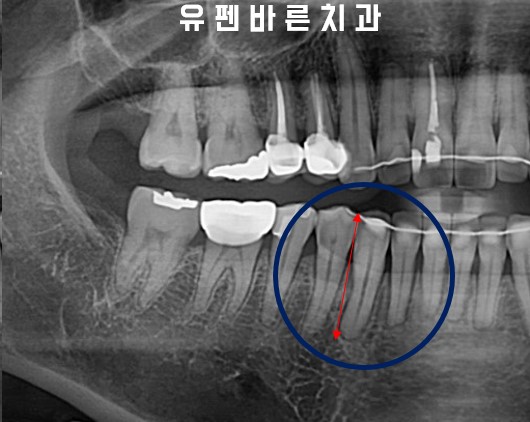

Adding buccal root torque on LR3

전,후 엑스레이 사진을 비교해 보시면

치아의 뿌리가 바로 서면서

교정 전, 후의 치아길이가

확연히 달라진 모습을

확인해 보실 수 있습니다!

엄청 앞으로 누워있던 치아를

인비절라인 교정을 통해

뿌리의 각도를 움직여

본래 치아의 모습으로

돌아왔습니다.